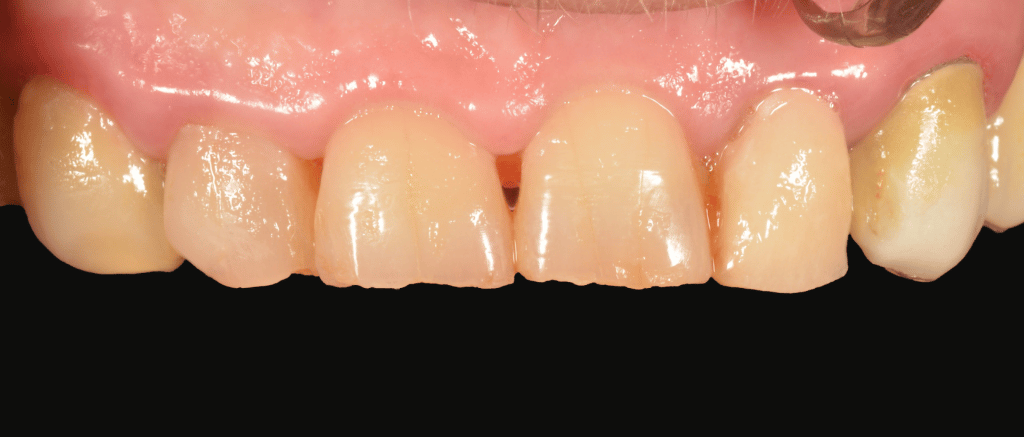

A resin provvisional crown is luted with temporary cement.

At the delivery the provissional is removed. Tissues are healty and, again, no bleeding is present.

provisional phase

removal of provisional for delivery

lateral